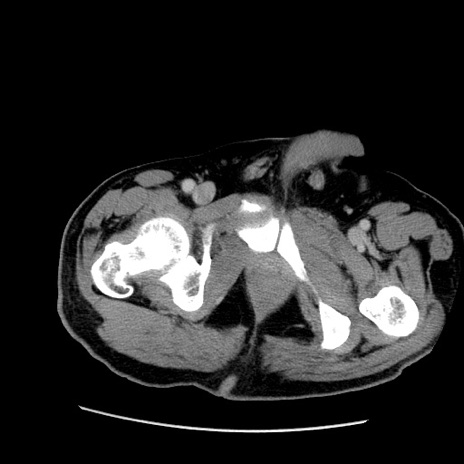

症例

冠状断像